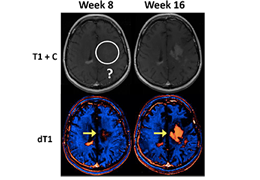

Eclipse 成像智能功能提供强大的处理能力和最佳质量的影像,同时减少质量错误并提高剂量效率。

凭借 AI、专有算法和先进的影像处理能力,提供出色的影像质量和无与伦比的诊断信心。

与标准影像处理相比,智能降噪功能可使客户降低辐射剂量,而不会损失影像质量。这在新生儿和儿科成像中尤其重要,在这种情况下以尽可能低的剂量成像至关重要。